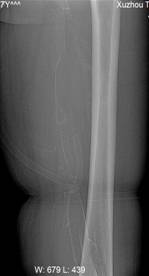

2、股骨头坏死

股骨头坏死是因为其供血障碍所引起。通过介入穿刺技术,以细小导管进入股骨头供血动脉血管,以改善微循环药物通过压力改变注入其中,原缺血的股骨头供血得到明显改善;术后再以扩血管、活血化瘀等药物静脉应用,辅以中药外敷并红外线理疗,进一步促进股骨头血液循环的好转,疼痛等临床症状得以明显好转,有效率达90%以上。介入治疗股骨头坏死是以改善股骨头血供为主要目的,起到延缓骨质坏死的进展,适用于一、二、三期患者;而对于二期囊变并有硬化圈的患者尚需要骨科髓芯减压手术,四期患者需要人工股骨头置换手术。

朱××,男,45岁,双侧股骨头坏死,左侧髋关节疼痛明显,不能独立行走,需使用止痛药物(图1,MR)。介入治疗术中造影(图2a)示:股骨头供血动脉分支稀疏,远端痉挛、股骨头骨质内无明显分支动脉血管;治疗后(图2b)造影见股骨头供血动脉分支血管明显增多,远端可见达股骨头骨质内,原髋关节疼痛消失,自行行走出院。

何××,男,6岁,儿童股骨头坏死,左侧股骨头骨骺坏死、骨质碎裂(图3),经治疗后骨骺骨质恢复(图4)。

图1 图2a 图2b

图3 图4